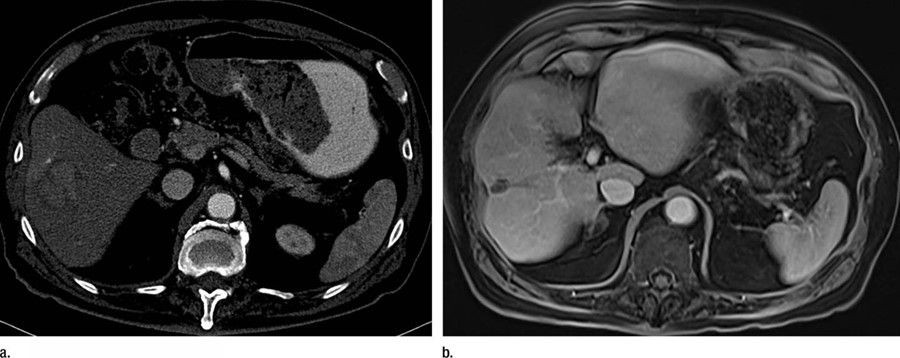

El avance de un fármaco brinda la supervivencia más prolongada en pacientes con cáncer de hígado no resecable

El ensayo IMbrave150 ha comprobado que la mediana de supervivencia global fue de 19,2 meses en los pacientes tratados con atezolizumab plus bevacizumab frente a 13,4 meses en los tratados con sorafenib solo, el tratamiento estándar actual. La supervivencia a los 18 meses fue del 52% con atezo + bev y del 40% en los pacientes tratados con sorafenib.

El atezolizumab es un fármaco inhibidor de los puntos de control inmunológico, que ayuda al sistema inmunológico a detectar y destruir el cáncer. El bevacizumab es una terapia de anticuerpos monoclonales dirigida que priva a los tumores de su suministro de sangre al prevenir el crecimiento endotelial, pero también mejora los efectos inmunológicos de atezolizumab.

Los nuevos datos, presentados en la Cumbre de Cáncer de Hígado 2021 de la Asociación Europea para el Estudio del Hígado (EASL), siguen a la publicación inicial de los datos del ensayo con 8,6 meses de seguimiento que encontraron que la supervivencia a los 12 meses fue del 67,2% con atezo + bev, frente al 54,6% de los tratados con sorafenib. Este nuevo análisis de supervivencia general descriptivo post-hoc incluyó 12 meses de seguimiento adicional del análisis primario.

El profesor Richard Finn, autor principal del estudio, explica que "IMbrave150 mostró un beneficio y seguridad de tratamiento clínicamente significativos y consistentes con 12 meses adicionales de seguimiento. La combinación proporciona la supervivencia más larga vista en un estudio de fase III de primera línea en cáncer de hígado no resecable avanzado, lo que confirma atezo + bev como un estándar de atención para el cáncer de hígado irresecable no tratado previamente".

"Estos son hallazgos muy importantes para el tratamiento de pacientes con cáncer de hígado irresecable --añade--. Muchos miles de pacientes en todo el mundo podrían beneficiarse de este tratamiento y puede considerarse un gran avance: la primera mejora en el tratamiento para este tipo de casos en 13 años y un tratamiento de larga duración esperado por los médicos".

El beneficio de supervivencia con atezo + bev frente a sorafenib fue generalmente consistente en todos los subgrupos y con el análisis primario. La tasa de respuesta objetiva actualizada con atezo + bev estuvo en línea con el análisis primario, con más pacientes que lograron una respuesta completa de lo que se informó anteriormente. La seguridad fue consistente con el análisis primario, sin nuevas señales identificadas.

"Ahora necesitamos entender qué es lo próximo en el cáncer de hígado de primera línea y cómo nos basaremos en estos datos para mejorar aún más los resultados más allá de los 19,2 meses que describimos --señala--. Además, debemos evaluar la eficacia de este régimen en las primeras etapas del cáncer de hígado irresecable".